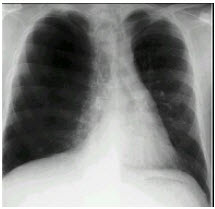

男,65岁,呼吸困难伴胸闷,胸片结果如图,最可能的诊断为()

A.气胸

B.肺结核

C.慢性阻塞性肺疾病

D.肺部感染

E.支气管扩张